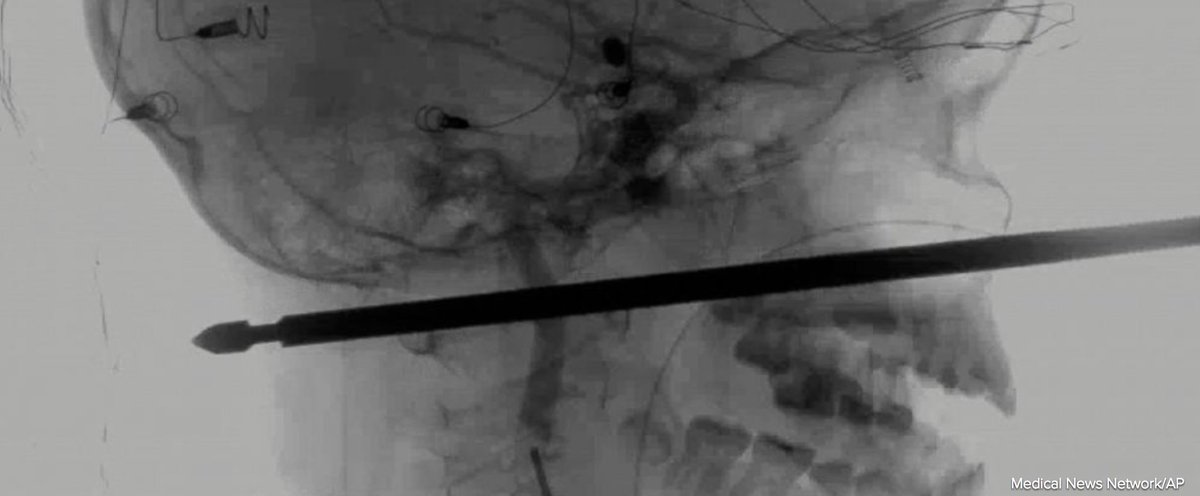

Say what you want about American healthcare, but if you get a skewer in your head, we will fix it.

He was more worried about the yellow jackets swarming him than he was the skewer. I don't blame him. They attacked and caused him to fall out of a tree house. He came out of it with very little swelling and a couple of band aides over the entry and exit wounds.

Damn he was lucky, his Guardian Angel was with him. By this xrays looks like it may be touching bone, but missed discs, arteries, not sure about facial nerves, but very lucky. Even luckier no one attemped to pull out until in hospital

1. That’s not the picture of the kid this story is about. 2. That’s an archery arrow with with a field point, not a meat skewer.

Yeah I was wondering the same thing. Doesn't look like any meat skewer I've ever seen.